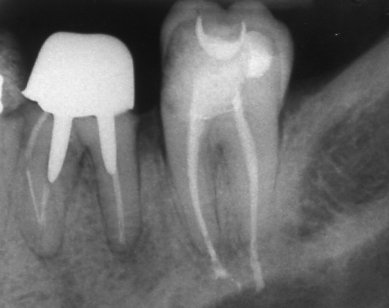

Ендодонтия